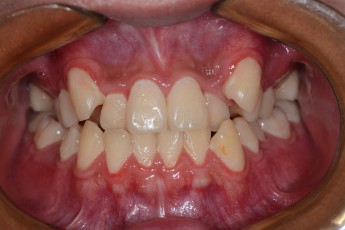

Before & After

- 덧니교정

Before

After